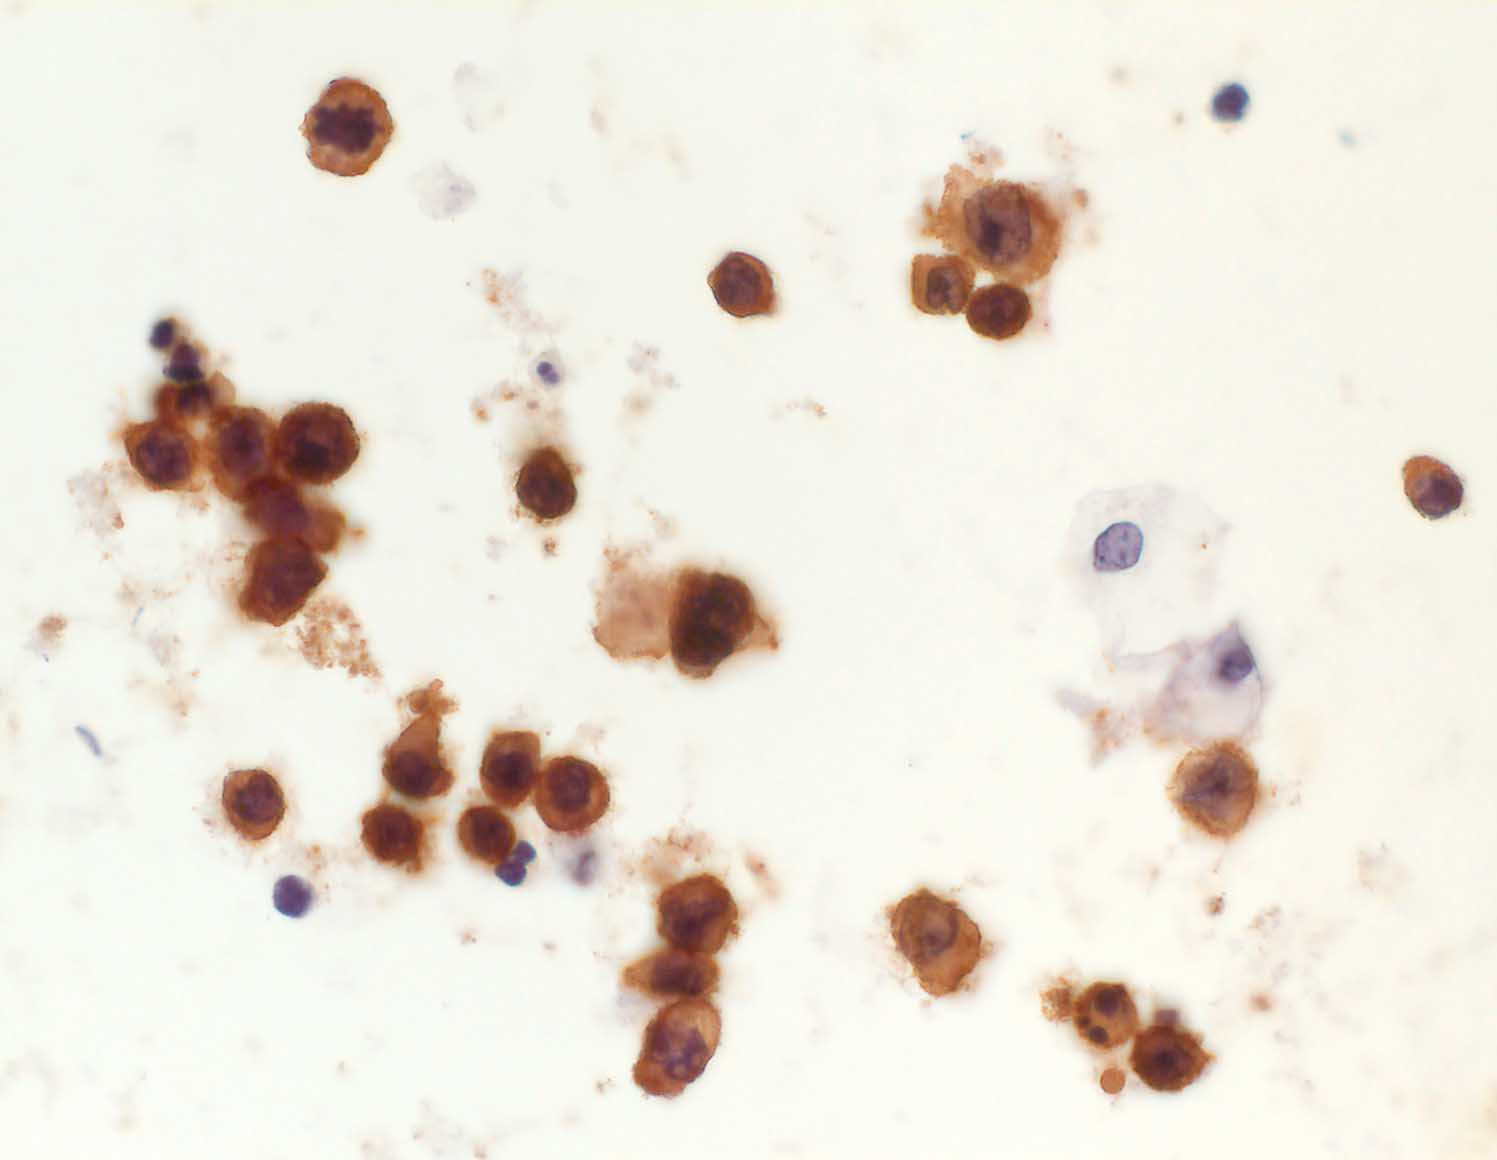

diffuses grosszelliges B-Zelllymphom

Urin

Urin: Die atypischen Zellen sind positiv für den Leukozytenmarker CD45.

Sämtliche Tumorzellen sind stark positiv für den Leukozytenmarker LCA, aber negativ für die Epithelmarker Ber-EP4 und Zytokeratin 20. Somit handelt es sich um Zellen eines grosszelligen Non-Hodgkin-Lymphoms, und nicht um Karzinomzellen.

Nieren-Tumor rechts. DD: Urothel-Ca.

Zytologie

Immunhistochemie

CD45 (LCA)

400